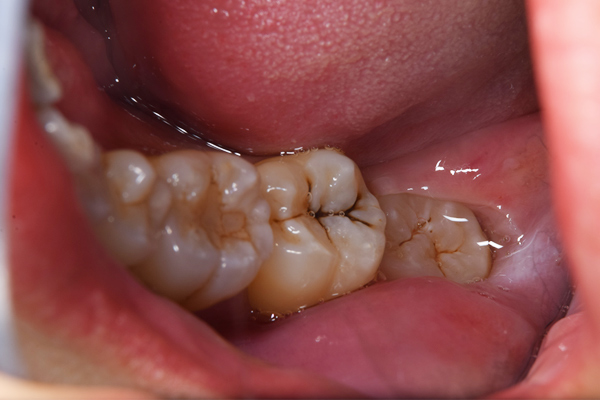

下顎の親知らずは右下のみはえています。まっすぐはえていますが、前の歯よりも低い位置にあるので、磨くのが難しそうです。舌側の歯茎がかぶっているのがみてとれます。

上顎の親知らずは頬の方を向いてはえています。こういうった親知らずはやはり磨くのがとても難しいです。